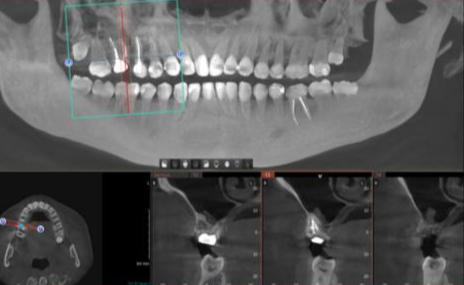

На кт в пикассо обнаружили вот такое (описание пока готовится). Специальнотприехали в крупный город из нашешо маленького. За 3 месяца там обошли по несколько лоров и стоматологов и все показывают пальцами друг на друга и говорят, что это не их профиль. Один умник выдвинул даже идею, что боли соматические и надо к психологу. Но дочь мучается явно, а не "соматически".

Я совсем не понимаю ничего не снимках, к сожалению. Что это за серые "яйца" над шестыми зубами? Гной? Воспаление? Новообразования? Как это убирать? Дочь измучилась!